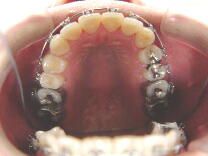

症例1 (10代 女性) 左右上下顎第一小臼歯抜歯例

初診から1年6ヶ月後